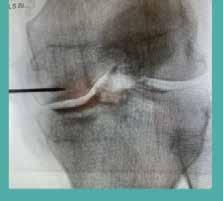

Stalled takeoff

It’s hard for Paso Robles dirt biker Primo Vargas to forget the memory of his fellow off-road rider being flung from his bike a decade ago during hill climbs in Pozo— breaking his back and neck in the process. But the life-saving impact of a medevac helicopter also left an indelible impression on him.

“We were able to call the police after we got [cell] service. It was really fast,” Vargas said. “He had brain swelling and brain bleeding. He would have died if we didn’t have a service like this in our area that they’re trying to get rid of.”

San Luis Obispo County has benefited from three kinds of aircraft support services for medical emergencies. From 2012, CALSTAR’s REACH Air Medical Services in Santa Maria helped the county.

Then from 2022, the California Highway Patrol helicopter began supporting law enforcement operations and patient rescue and transportation needs as an Advanced Life Support Rescue vehicle.

From 2020, the Mercy Air 34 helicopter operated out of its Paso Robles base as the only air ambulance in the county, helping critically ill and injured people after receiving 911 calls and requests for hospital transfers.

In early September, Mercy Air’s parent company Air Methods announced that it would close the Paso Robles base on Nov. 4.

For Paso Robles’ Vargas, a helicopter service like Mercy Air 34 is the difference between saving someone and spending a lifetime thinking, “What if?”

While he’s sought the service of other helicopter medevac operators over the last 10 years and more, Vargas told New Times he’s upset by Mercy Air 34’s proposed closure.

“San Luis Obispo County is, for one, a pretty well-to-do county,” he said. “But in the recent years, a lot of the medical aspects of this county have been going through the gutters. … If you’re faced with a disaster, you don’t want to have to think that you’re going to wait an additional hour or two for the closest medevac to get to you.”

Air Methods spokesperson Denise

Coffman told New Times the Paso Robles base isn’t sustainable any longer because of the lack of reimbursement increases to the state’s Medi-Cal and federal Medicare programs.

“Medicare has not increased rates in more than 20 years and currently reimburses only about 60 percent of our costs,” Coffman said. “Medi-Cal currently pays a flat rate of $1,800 per transport plus mileage, which covers less than 35 percent of the actual cost of a patient transport.”

Long-term volume trends also contributed to the shuttering. Coffman said that MediCal patients make up 40 percent of Mercy Air 34 transports, while Medicare patients comprise 30 percent.

“That means 70 percent of our transports are reimbursed at less than half of what it costs to provide the service,” she said. “At the same time, operational costs—such as fuel,

labor, aircraft, and parts—continue to rise, compounding the financial challenges.”

Mercy Air has served California and Nevada from different bases for 35 years.

The Paso Robles base is the only one closing. Coffman added that financial strain caused by insufficient Medi-Cal and Medicare reimbursement levels puts all air medical bases at risk.

County officials confirmed that there is no equivalent service to the ones provided by Mercy Air 34. Over its five-year tenure, the helicopter enhanced patient care with a new automated CPR device and blood transfusion capabilities.

The latter service, which isn’t provided by Santa Maria’s CALSTAR 7, makes Mercy Air 34 the only outof-hospital unit capable of blood transfusion.

SLO County Health

Agency spokesperson Olivia Montiano told New Times that the county plans to work with California Highway Patrol and other

agencies to address future rescue and air paramedic needs.

“We are saddened by the forthcoming departure of Mercy Air 34,” she said. “This change presents challenges for those in our rural community as well as those who need specialty care out of the area, such as burn patients or pediatrics care.”

Mercy Air 34’s impending closure concerns Cal Fire SLO County Unit Chief John Owens. So much so that he wrote a letter to Air Methods urging it to reconsider its decision or at least work with local and regional partners to come up with alternate solutions to fill the gap.

“Critically ill or injured patients who once reached higher-level care within 45 to 60 minutes may now face ground transports of two to three hours,” Owens wrote.

“The ability to bypass local facilities and transport directly to specialized trauma, burn, or pediatric centers is no longer available within our county borders.”

According to his letter, people who are going to be most affected are residents of Heritage Ranch, Oak Shores, Shandon, Creston, the Carrizo Plain, and the coastal communities outside of city centers who already face long drive times to reach the closest emergency department.

Visitors traveling along Highways 41, 46, 58, and 166, and people recreating in state parks and Los Padres National Forest would face similar impacts.

The absence of Mercy Air 34’s services, Owens’ letter added, would also increase the burden on ground ambulances and neighboring counties.

“Its crews have worked side by side with our firefighters, paramedics, and local hospitals to provide rapid transport and advanced medical interventions that cannot be duplicated by ground-based resources alone,” Owens wrote.

“The loss of this service leaves a gap in our county’s emergency medical system at a time when every minute can mean the difference between life and death.” ∆

SOLE SHUTTERING Air Methods confirmed that Mercy Air’s Paso Robles base is the only one slated for closure despite the company having other air bases scattered in California and Nevada. Mercy Air 34 will be pulled from service in November because of insufficient